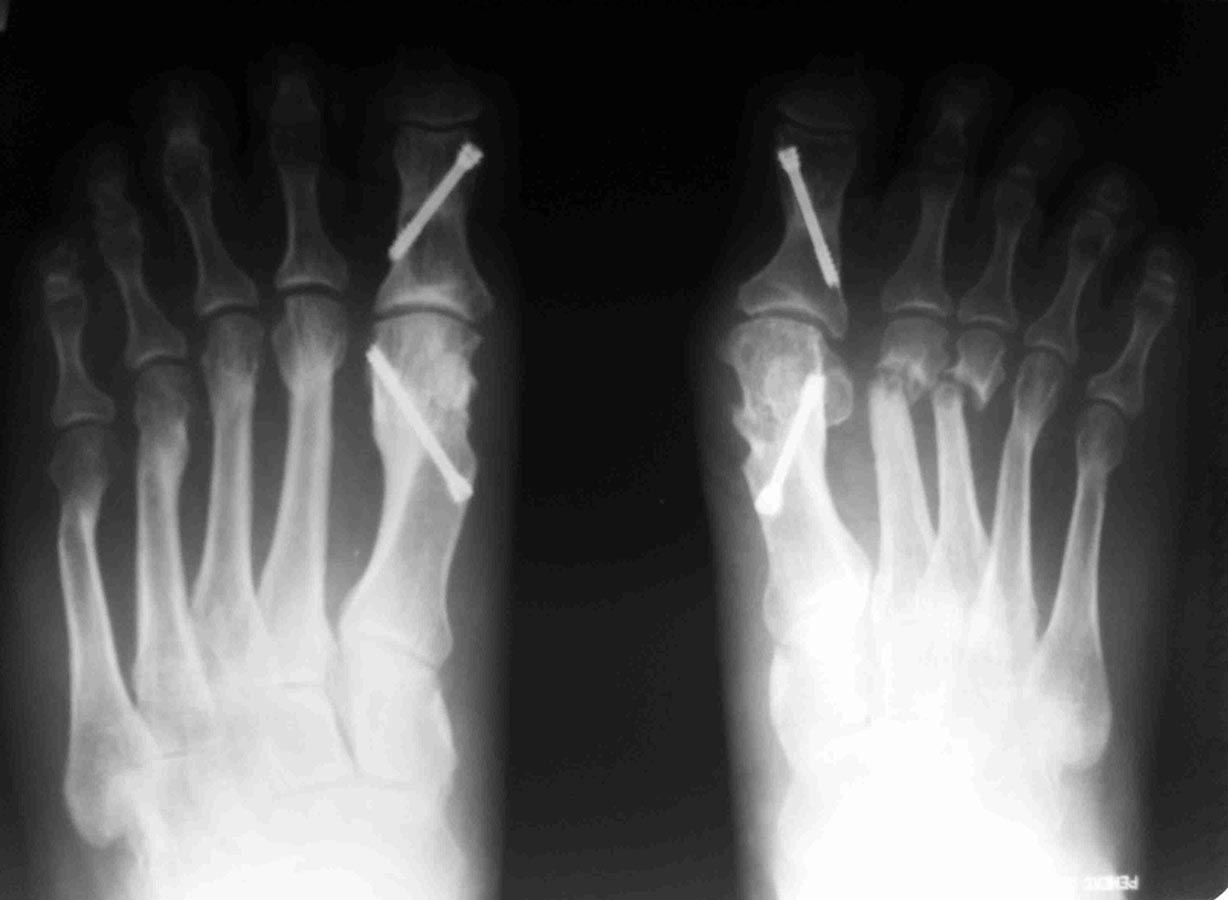

Уважаемые коллеги, я понимаю, что уже утомил вас оперированными стопами,

но помогите еще с одним случаем

Женщина около 50, активная, оперирована 1 год назад. Тип остеотомии в

выписке не указан (похоже с 1-го по 5-ую + фаланги). Сожалею. что фото

стопы не удалось выложить, клинически - выраженная девиация всех пальцев

стопы слева. Что предпринять? Латеральный релиз, утягивание (лучшего

синонима не нашел) медиальной капсулы+остеотомии 4-5 с нормальной

повязкой? 1-ый луч - SERI (для жесткости остальных- к нему притянуть),

но, головка и так скомпрометирована (или это не брать в расчет?)+

освежение ложняков+ коррегирующая остеотомия 4-5 Weil с фиксацией винтом

(или без фиксации?). С фалангами что делать? Кажется,

что ничего?